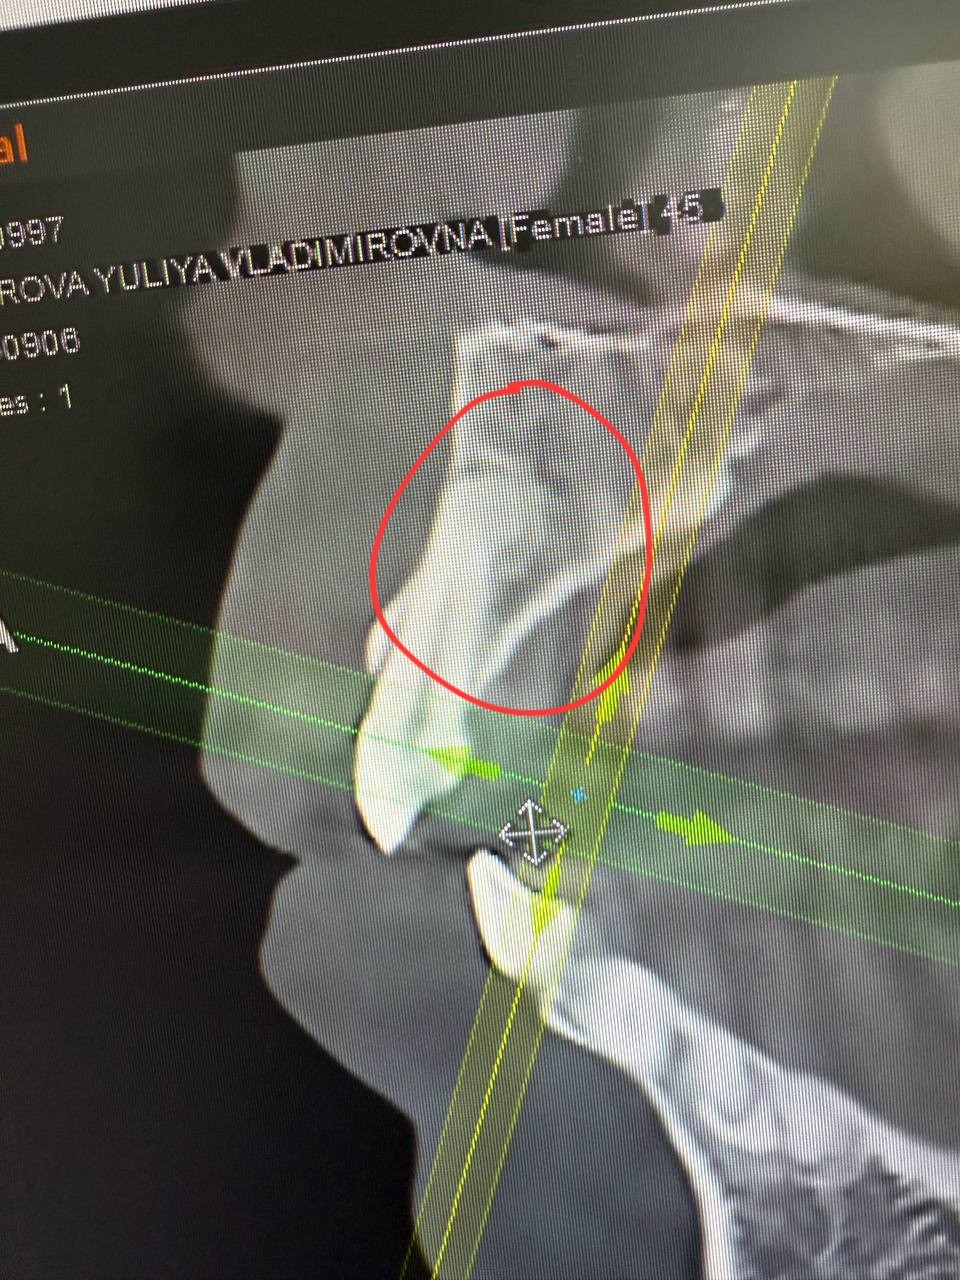

Здравствуйте, прохожу протезирование коренных зубов. КТ показало образование на корнях зубов 12 и 43. Врач затрудняется ответить что это может быть.

Вверху предположительно цементома, а внизу предположительно одонтома. Это все доброкачественные состояния. У вас получится прислать все содержимое диска с КТ через файлообменник, например, гугл-диск?

Да, конечно. Ранее в 2023 году я наблюдалась относительно остеомы в границах 38, вы должны были её заметить, она большая. Делала МСКТ нижней челюсти: очаг остеосклероза был поставлен в итоге диагноз, и аналогичный очаг поменьше в районе 35. Про передние зубы в описании ничего не указано и врач тогда не отмечал ничего дополнительно. Вопрос а был ли "мальчик" уже тогда?

Мой лечащий врач склонен считать что это цементно костная дисплазия и в верху и внизу. Предлагает не трогать и смотреть в динамике как образование будет себя вести в дальнейшем (это вверх). Низ просто под наблюдением, там коронок не будет. Если будет рост на корне 12, возможна резекция корня с последующей гистологией. Как бы решать проблему по мере поступления.